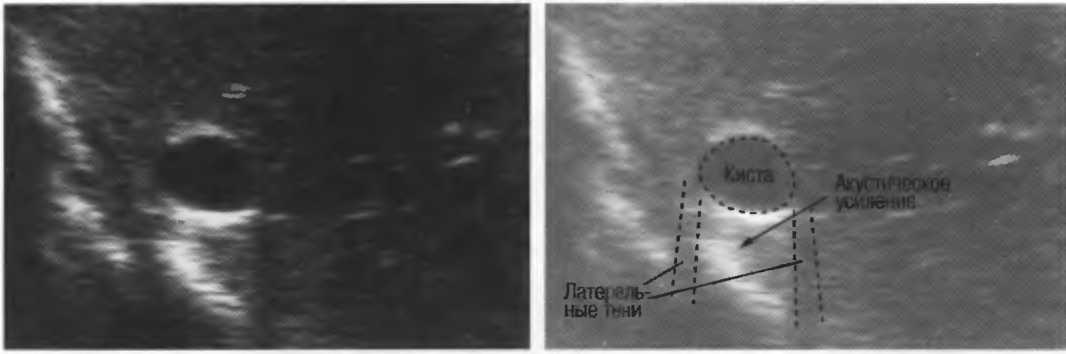

Кисты

Киста, как правило, визуализируется в виде анэхогенной зоны, при этом структуры, расположенные за кистой, обычно усилены: полость кисты анэхогенна, поскольку в ней нет структур с различным акустическим сопротивлением. В результате того что жидкость не поглощает ультразвук в такой же степени, что и ткань, эхо-сигналы от расположенных позади кисты структур гиперкомпенсированы сканером и выглядят усиленными — появляется эффект усиления задней стенки (рис. 14а,б).

Киста определяется в виде анэхогенной зоны с усилением по задней стенке. Если в кисте есть внутренние зхоструктуры, то они могут быть реальными или являться артефактами.

Рис. 14а. Заполненная жидкостью киста: полость кисты анзхогенна, имеется усиление задней стенки.

Структура, наподобие содержащей чистую жидкость кисты, визуализируется как анэхогенная зона. Стенки кисты отражают ультразвуковые сигналы под углом, и информация не поступает назад в трансдьюсер. В результате этого появляются боковые тени, но сзади кисты имеется усиление эхосигналов (усиление задней стенки) (рис. 15).

Рис. 15а. Киста печени: жидкость внутри чистая, анэхогенная. Стенки кисты отражают ультразвук под углом от датчика, вызывая появление боковых теней.